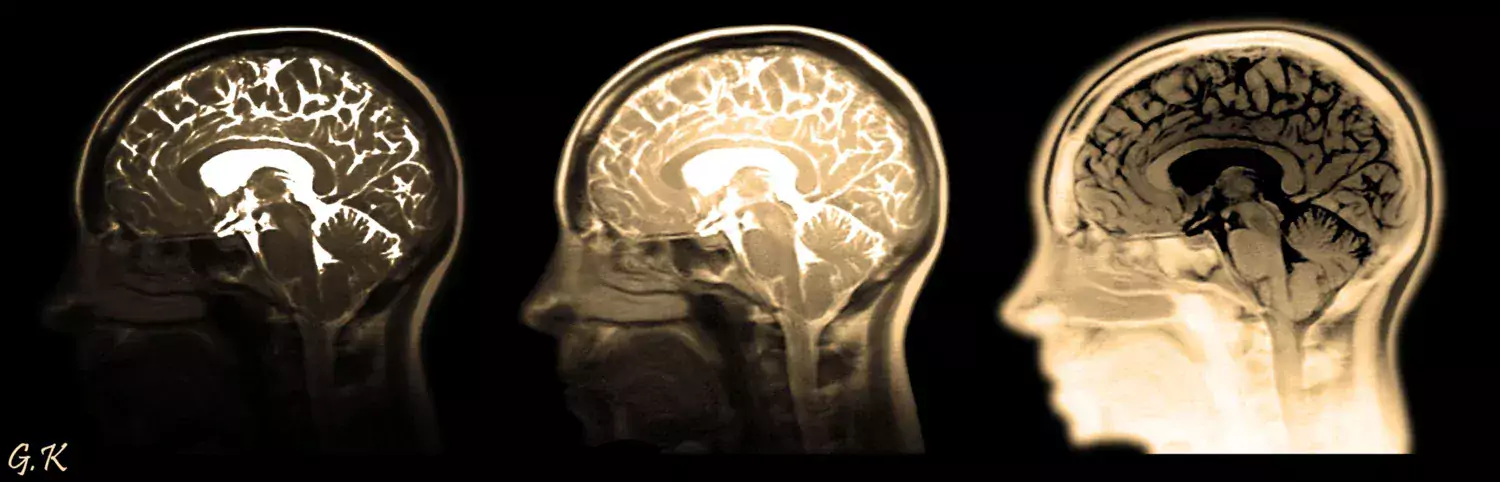

Our research focuses on the effects of normal and pathological aging on structural, molecular, mechanical and functional brain integrity, in relation to cognition. We also study genetic, physiological and lifestyle factors that modulate age-related brain and cognitive changes. We use a broad range of Magnetic Resonance Imaging (MRI) techniques and positron emission tomography. We also develop deep learning methods that we apply to neuroimaging.

Our research focuses on the effects of ageing on structural, molecular and functional brain integrity, in relation to cognition. We also study genetic, physiological and lifestyle factors that modulate age-related brain and cognitive changes. We use a broad range of Magnetic Resonance Imaging (MRI) techniques and positron emission tomography.

The focus of our research is two-fold: we study (1) the effects of normal and pathological aging on structural, molecular, biomechanical and functional brain integrity, in relation to cognition, (2) genetic, physiological and lifestyle factors that modulate age-related brain and cognitive changes.

We use a broad range of magnetic resonance imaging techniques (MRI) and positron emission tomography (PET). To reach a better understanding of the neural underpinnings of cognitive performance, we use advanced techniques and methods such as: